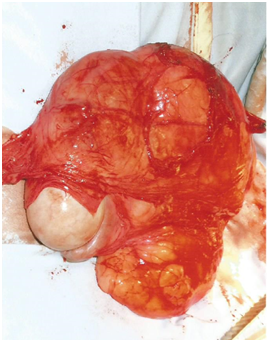

A 77years old gentleman presented to his GP with a non-tender long-standing scrotal swelling for the last 10years. He had a previous anterior resection for bowel cancer. On examination, in the outpatient’s clinic, the right hemiscrotum contained a small hydrocele, but also a firm mass which prompted urgent ultrasound scan. The scan showed a soft tissue mass in close relationship to- but sparing the testicle, measuring 8x4cm (Figure 1). Given the patient’s age and the nature of the mass suggested by imaging, he was advised on surgical exploration and consented for possible orchidectomy, pending on intraoperative findings, and direct inspection of the mass. Surgical exploration of the scrotum was performed. The testicle and epididymis looked normal. A lump of fatty tissue mimicking an inguinal hernia was noted protruding down from the inguinal canal. After careful dissection, a hard mass was found adjacent to and engulfing the spermatic cord. Orchidectomy was performed, ensuring wide excision of the mass and its surroundings.

Figure 1 scrotal ultrasound finding. Large soft tissue mass separate from testicle.

Generally, the scrotum and its contents can be reliably imaged using ultrasonography, contrasten chanced CT and MRI.3 In this case, ultrasound scan reliably distinguished he suspect mass as being separate from the testicle (Figure 1). However, diagnosing LSC via imaging studies is difficult. For example, ultrasound cannot reliably distinguish between well differentiated liposarcoma and benign lipoma.11 Further, CT and MRI imaging commonly misdiagnose LSC as a hernia, due to its fatty composition.6 Hence, LSC is usually diagnosed intra- or post-operatively.1